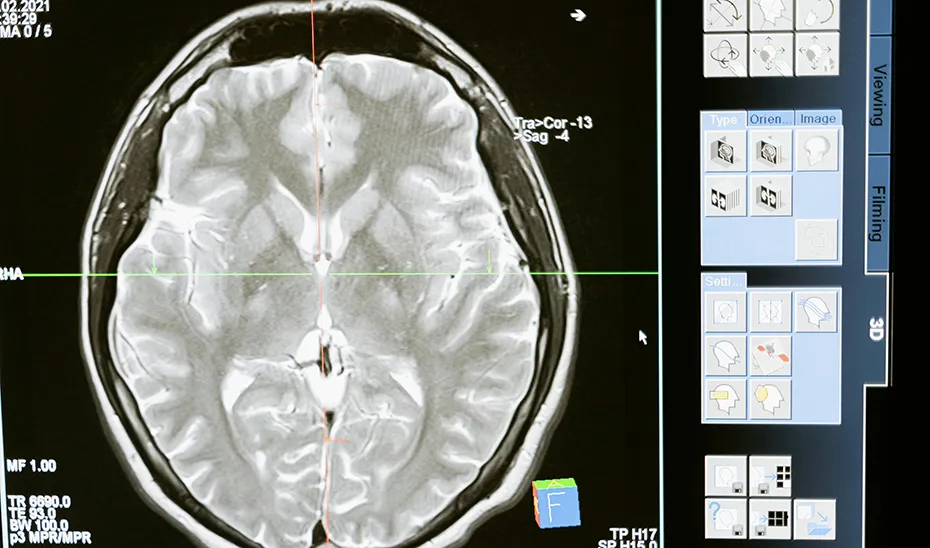

El Consejo de Gobierno ha tomado conocimiento de las actuaciones realizadas por la Consejería de Salud y Consumo para la prevención y recuperación de los episodios de Ictus coincidiendo con el Día Mundial del Ictus, que se celebra cada 29 de octubre. Desde 2019, el Gobierno andaluz ha apostado por la creación de nuevas Unidades de Ictus, la implantación de tecnologías como el Centro Andaluz de Teleictus (CATI) y la formación de profesionales sanitarios, entre otras medidas. Estas acciones buscan mejorar la atención a esta patología, que constituye una de las principales causas de mortalidad y discapacidad a nivel global.

El ictus es una enfermedad grave que ocurre cuando se interrumpe el flujo sanguíneo hacia una parte del cerebro, lo que provoca la muerte de las células cerebrales. Existen dos tipos principales de ictus: el isquémico, que representa el 80% de los casos y ocurre cuando un coágulo bloquea una arteria, y el hemorrágico, que se produce cuando un vaso sanguíneo se rompe. Los síntomas incluyen dificultad para hablar, debilidad en un lado del cuerpo y pérdida de la visión. Una atención rápida y adecuada es esencial para reducir las secuelas.